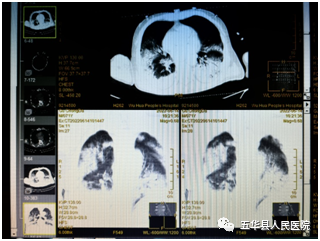

李震东教授提醒:大便习惯性状改变是肠道疾病的警报,及时行肠镜检查是王道。 李震东:肝胆外科主任医师,副教授,博士,硕士生导师。主研大肝癌、胆管癌、胰腺癌及肝胆胰脾良性肿瘤。挂任外科部主任,驻点普外科,每周二上午出门诊。 叶禄伟常务副主任带领完成首次应用俯卧位通气治疗重症病人 近日ICU收治一例重症肺炎的老年患者,CT提示双侧肺部感染明显,经常规气管插管接呼吸机辅助通气、抗感染、免疫增强等治疗氧合状况仍差。

患者肺部CT图像

挂职专家叶禄伟查房后结合患者呼吸机支持参数情况、病人体征、及床旁超声肺部探查情况,提出实施俯卧位通气治疗患者。此前ICU未开展过该项技术,缺乏进行俯卧位通气相应的专用病床、翻身单、软枕、硅胶枕等物品,增加俯卧位通气的操作难度,但考虑到若能实施俯卧位通气确能有助于患者的氧合,有利于抢救的成功。16日上午,在叶禄伟专家指导下,利用科室现有的小尺寸翻身单拼接、翻身枕头等物资创造条件,完成了俯卧位通气的实施。